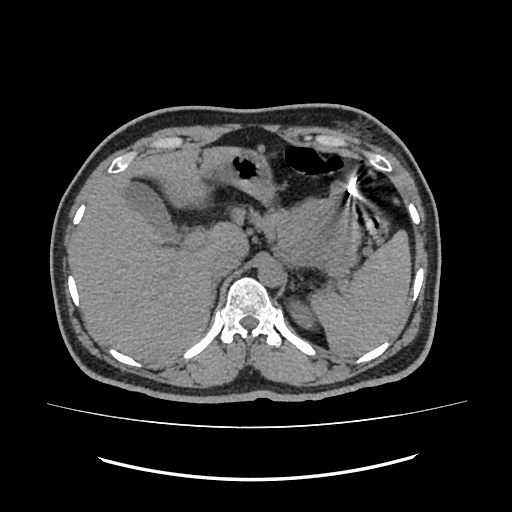

LUNG MASS BIOPSY, 45Y F

LUNG MASS BIOPSY, 70Y F

PANCRATIC BIOPSY, 34Y M